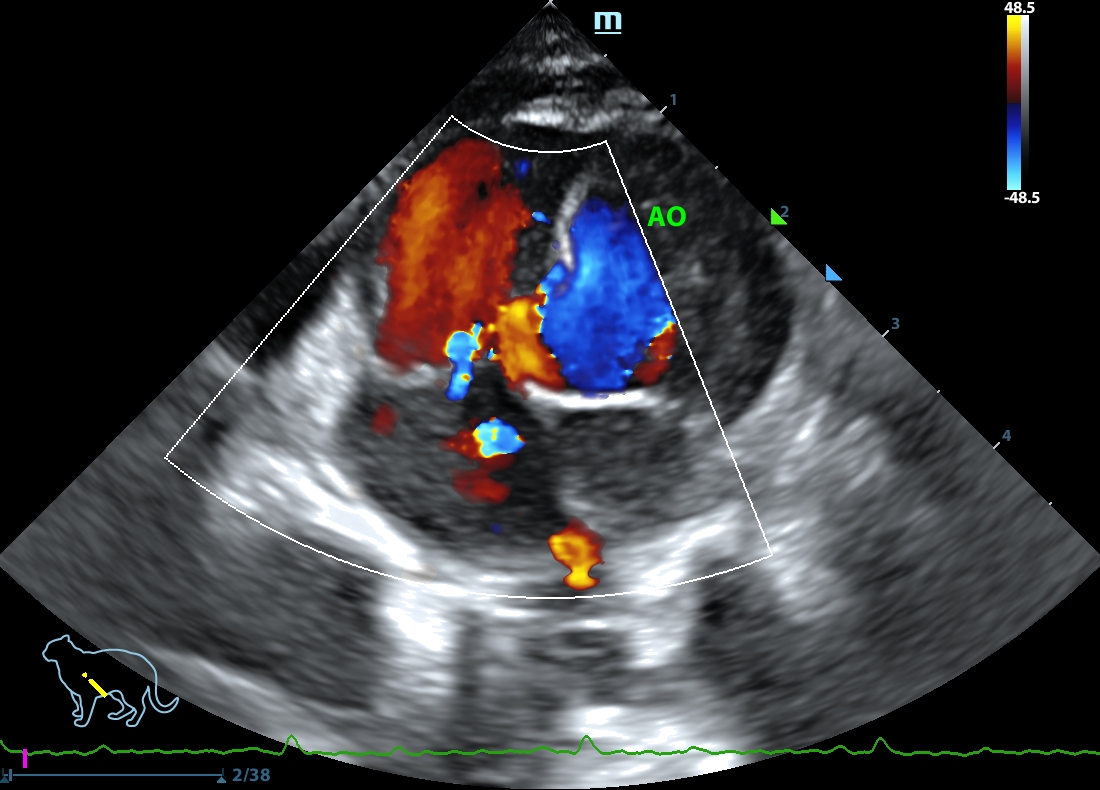

202507112248300160CARD.JPG